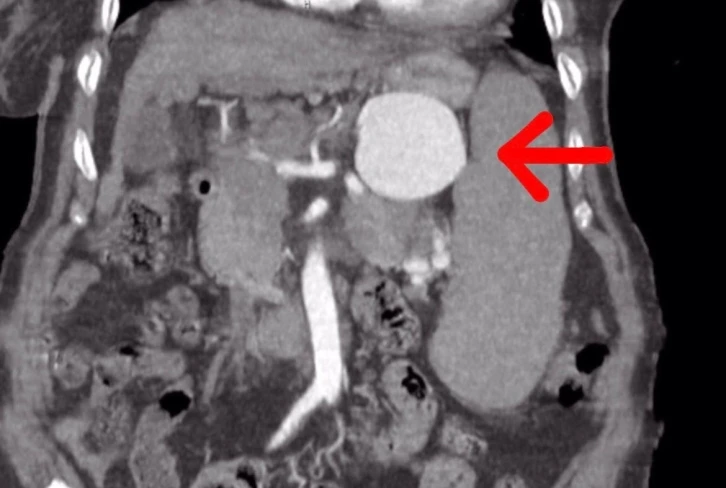

Yapılan ameliyat ile ilgili gazetecilere açıklamalarda bulunan Op. Dr. Volkan Burak Taban, hastanın gastroenteroloji kliniğinden kendilerine geldiğini, dalak arterinde ciddi bir anerizma şüphesinden bahsedildiğini söyledi. Değerlendirmeler sonrası ilaç tetkikleri istediklerini belirten Dr. Taban, "Yapılan tomografide teyzemizde dalak arterinde oldukça geniş dev diyebileceğimiz anerizmanın yani baloncuklaşmanın olduğunu gördük. Normalde dalak anerizması diyebilmemiz için baloncuklaşma diyebilmemiz için 20 milim yani 2 santimin üstüne çıkması lazım. Ama gördüğümüzde bizde şaşırdık. Çünkü yaklaşık 7 santimi geçen bir dalak anerizması vardı. Hastanın bu anerizmanın içerisinde tamamen kan dolduğu için her an patlama riski vardı. Allah korusun hastanın hayatını kaybetme riski ile de karşı karşıyaydık. Hasta ile ilgili hemen multidisipliner olarak bir değerlendirme yaptık. Hem gastroenteroloji, hem genel cerrahiden Serhat hocamız, hem radyoloji kliniğimiz ile beraber değerlendirme yaptık. Hastamızın 15 yıldır mücadele verdiği bir karaciğer sirozu da bizim kararlarımızda etkili oldu” dedi. “Hasta Şırnak’ta tedavi olmak istedi”

75 yaşındaki hastanın Şırnak’ta ameliyat edilmesinin riskli olduğunu ve bu durumu hem hastaya hem de hasta yakınlarına söylediklerini aktaran Dr. Taban, "Hastamız ve yakınları yıllardır hastanemizde tedavi olmak istediler. Bizde hastamıza açık cerrahinin ilk etapta riskli olabileceğini düşündük. Çünkü karaciğer sirozuna bağlı ve diğer hastalıklara bağlı olarak kan değerlerinde inanılmaz derecede bir bozukluk vardı ve cerrahi oldukça riskliydi. Biz öncelikle anjiyo yoluyla kasıktan girerek dalak anerizmasına ulaşıp, dalak anerizmasının içerisini kapatmayı ve dalak damarına bir stent koyarak oradaki anerizmanın patlamasını engellemeyi çalıştık. Anjiyomuz yaklaşık 1,5-2 saat sürdü. Anjiyo salonuna aldık hastamızı, anjiyo sırasında ne kadar uğraşsak ta dalak damarı o kadar genişlemişki kendi etrafındaki damarlar ile beraber döndüğü için dalak damarını bir türlü kateterize edemedik. Dalak damarının içerisine ulaşsak da ardına ulaşamadık. Yaptığımız tekrar değerlendirmesinde hastamızın ameliyat edilmesinin daha doğru olacağını düşündük. Hastamızı açık cerrahi vakasına aldık. Açık cerrahi vakasında genel cerrahi ile birlikte, önce karından ufak bir keski ile girdik. Girdiğimizde karşılaştığımız manzara aslında tomografide gördüğümüz manzaradan veya anjiyoda gördüğümüz manzaradan daha da kötü haldeydi. Dalak damarı anerizmasını onararak hastamızı ameliyattan çıkardık. Ameliyat sonrasında da hastamızın bir yoğun bakım ihtiyacı olmadı. Servise aldık. Bundan sonraki değerlerimize baktığımızda da ciddi bir kan ihtiyacı olmadı. Daha sonraki kontrol kanlarımızda gayet iyi olduğu gözüküyor" dedi.